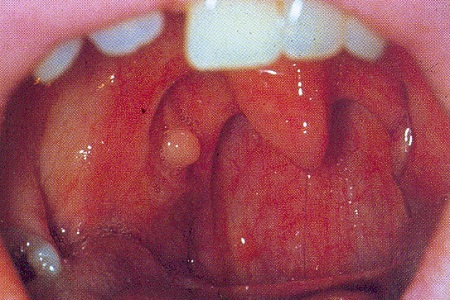

Киста может появиться в различных участках миндалин – как на их поверхности, так и внутри них. Она представляет собой непрозрачное круглое образование, похожее на шарик, белого цвета, эластичное и подвижное. Иногда отсутствуют признаки воспаления окружающих тканей.

Мукоцеле, также известная как ретенционная киста миндалины, может возникать как у детей, так и у взрослых, часто развиваясь на фоне длительных и хронических заболеваний носоглотки. Внешне она представляет собой круглую образование, покрытую тонкой слизистой оболочкой, что делает ее подверженной постоянным травмам.

Изначально внутри мукоцеле находится жидкое, клейкое содержимое, которое при постоянных травмах и воспалении может стать гнойным. Гнойная киста на миндалине начинает вызывать болевые ощущения и причинять много дискомфорта пациенту.

С виду это выглядит как белое или бледно-желтое уплотнение размером до 10 мм. Обычно оно не вызывает болезненных или других неприятных симптомов, поэтому часто остается незамеченным. Единственный способ удаления — хирургический.